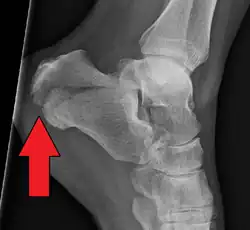

A suspeita surge no exame físico e é confirmada com radiografias convencionais ou com tomografia. Radiografia convencional é geralmente a ferramenta de avaliação inicial quando se suspeita de uma fratura do calcâneo. As radiografias recomendadas são (a) axial, (b) anteroposterior, (c) oblíqua e (d) com flexão dorsal e rotação interna do pé. Entretanto, a radiografia convencional é limitada para visualização da anatomia do calcâneo, especialmente na articulação subtalar, que é melhor visualizada com uma tomografia.[2]

O Ângulo de Gissane, ou "Ângulo Crítico", é o ângulo formado pelas encostas descendente e ascendente da superfície superior do calcâneo. Em uma radiografia lateral, um ângulo de Gissane> 130 ° sugere fratura da superfície da articulação subtalar posterior. O ângulo de Bohler, ou o "Tuber Angle", é outro marco anatômico normal visto nas radiografias laterais. É formado pela intersecção de 1) uma linha desde o ponto mais alto da faceta articular posterior até o ponto mais alto da tuberosidade posterior, e 2) uma linha a partir do primeiro até o ponto mais alto da faceta articular anterior. O ângulo de Bohler é normalmente de 25 ° a 40 °. Um ângulo diminuído é indicativo de uma fratura do calcâneo.[3]